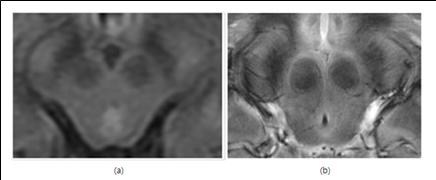

▲1.5T MRI(a)로 본 뇌 영상과 7T MRI로 촬영한 영상(b). 선명도에서 큰 차이를 보인다